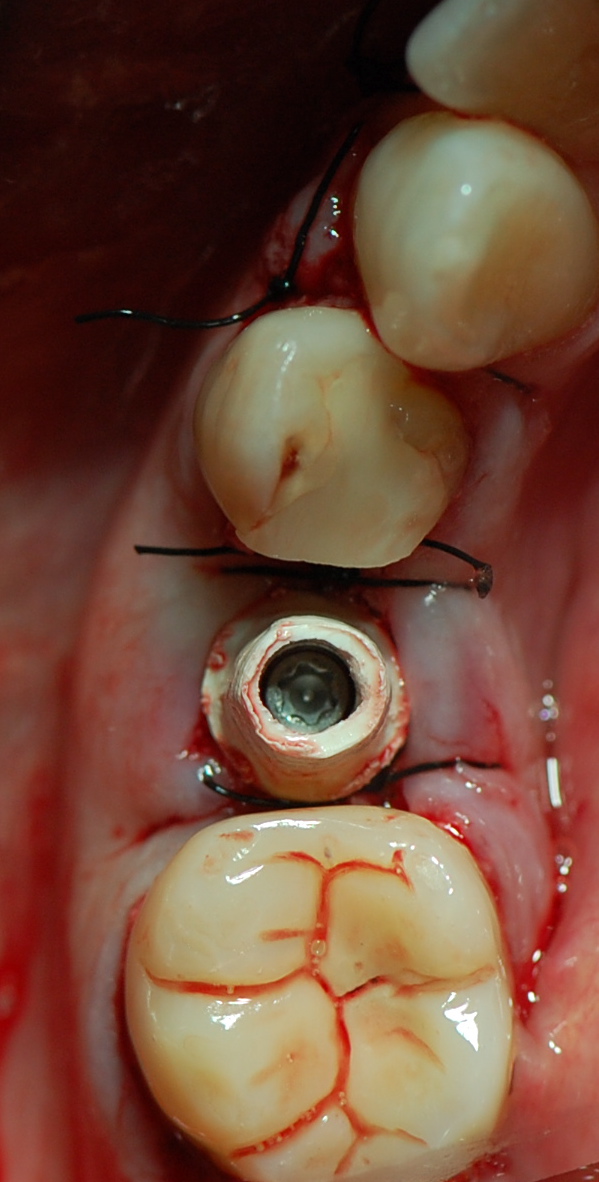

TAG: Post-estrattivo con carico immediato